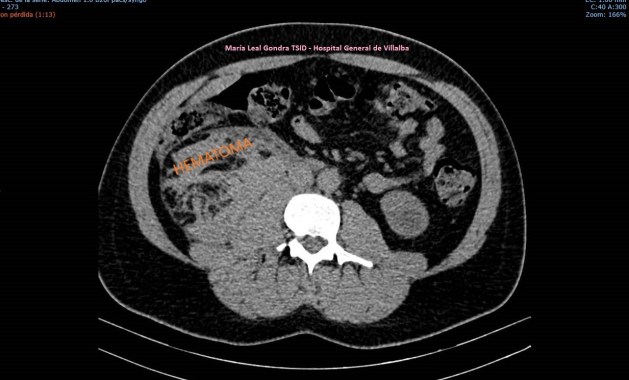

Se realiza Tc con contraste para completar estudio de extensión, en el que se confirman los hallazgos visualizados en la ecografía incluido el nódulo metastásico umbilical (FIGURA 8).

8